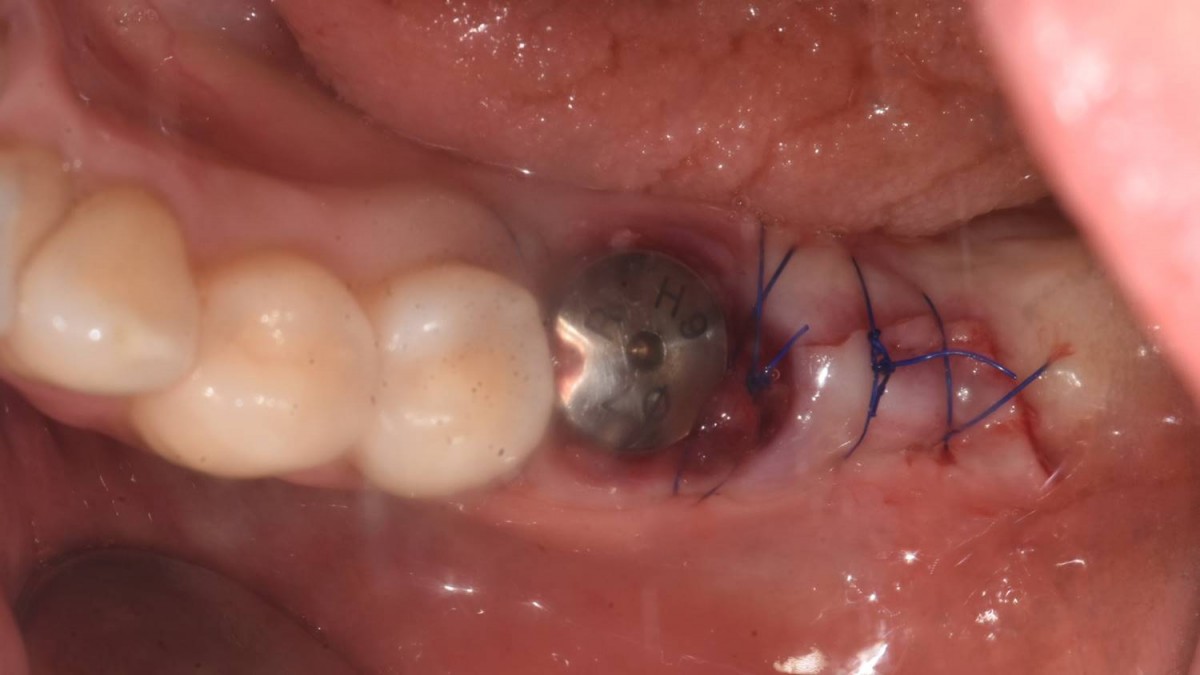

▲post-op panoramic radiograph.

▲. Panoramic radiograph after implant placement in the maxilla.(3 weeks after implant placement in the mandible)